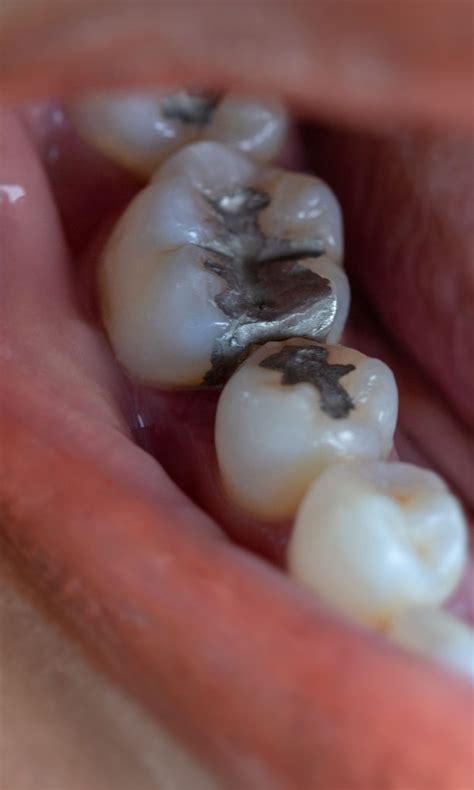

Respuesta: En el pasado, predominaban las amalgamas metálicas, que, aunque eran duraderas, presentaban preocupaciones estéticas y de biocompatibilidad. Hoy en día, los materiales de relleno más comunes son las resinas compuestas y los vidrios ionómeros. Las resinas compuestas ofrecen una estética superior, ya que se pueden pigmentar para asemejarse al color del diente natural, mientras que los vidrios ionómeros son apreciados por su liberación de flúor y su capacidad de adherirse a estructuras dentales.

| Material | Época | Características | Ventajas | Desventajas |

|---|---|---|---|---|

| Amalgama de Mercurio | Siglo XIX - XX | Compuesto de mercurio y otros metales | Durabilidad, resistencia | Toxicidad potencial, estética pobre |

| Resina Compuesta | Siglo XX - Actualidad | Compuesto de resina y partículas de relleno | Estética, adhesión | Menor durabilidad que la amalgama |

| Ionómeros de Vidrio | Siglo XX - Actualidad | Vidrio y ácido poliacrílico | Liberación de flúor, adhesión | Menor resistencia al desgaste |

| Nanomateriales | Siglo XXI | Partículas a escala nanométrica | Estética mejorada, durabilidad, antimicrobianos | En desarrollo, costo puede ser mayor |